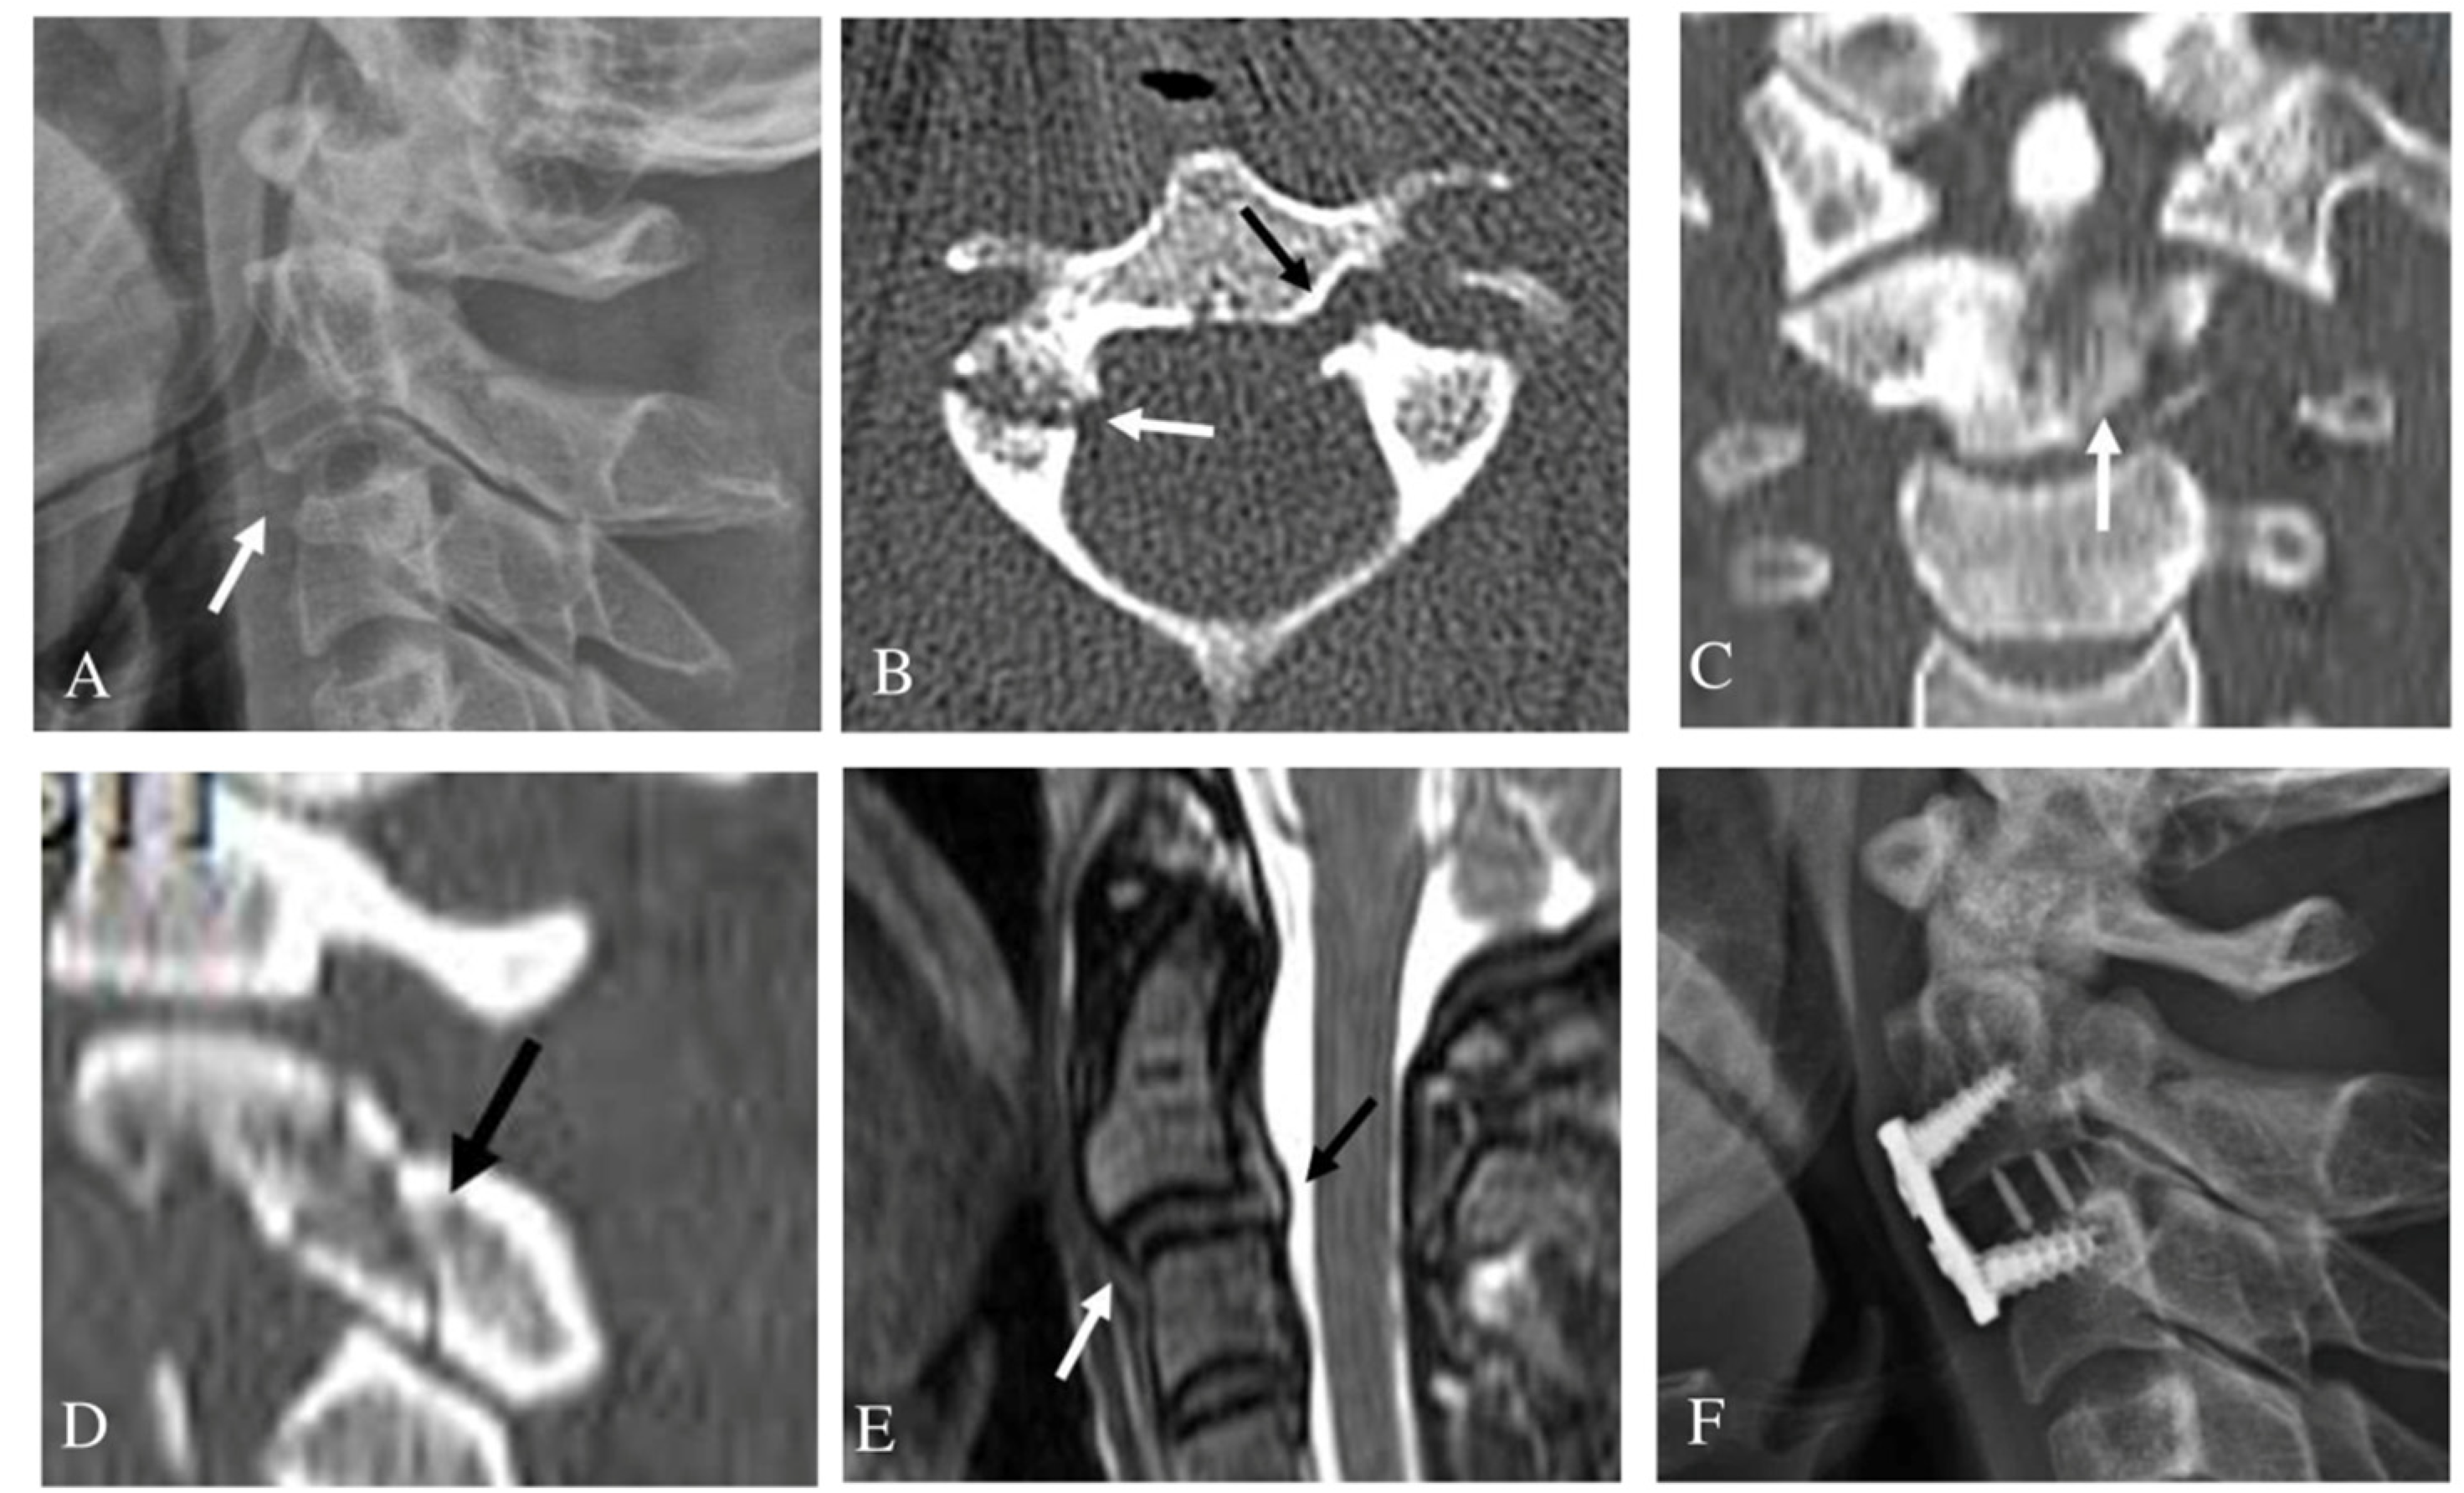

3.2. Unilateral Pedicle Fracture